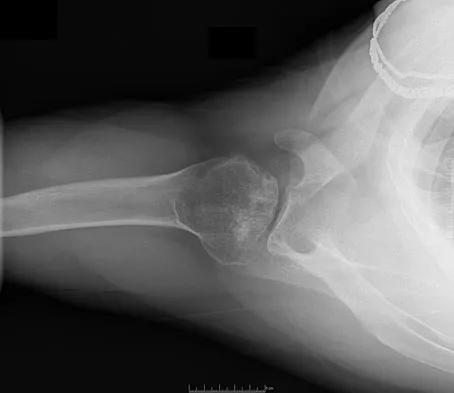

Figure 44 shows the radiograph of an 11-year-old girl who has hip pain. Further diagnostic workup should include

Explanation

The patient has severe acetabular protrusio, a condition that is frequently associated with Marfan syndrome. An echocardiogram is necessary to rule out the most serious consequence of this syndrome, aortic root widening, which can lead to aortic valve dysfunction or fatal aortic rupture. An electromyogram may be indicated for Charcot-Marie-Tooth disease, which is associated with acetabular dysplasia, but not protrusio. The renal ultrasound, the MRI scan, and the biopsy would be of no value in this patient. Protrusio can also be seen in patients with osteogenesis imperfecta and juvenile rheumatoid arthritis. Steel HH: Protrusio acetabuli: Its occurrence in the completely expressed Marfan syndrome and its musculoskeletal component and a procedure to arrest the course of protrusion in the growing pelvis. J Pediatr Orthop 1996;16:704-718.